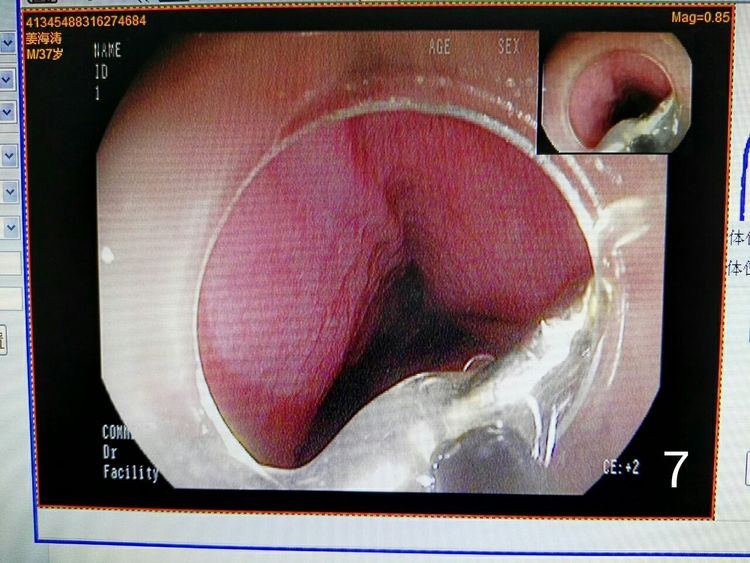

图7显示异物钳抓取异物